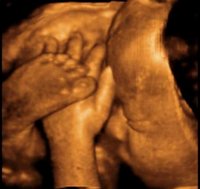

4Dエコー:超音波検査で胎児の表情や血管を立体的にリアルタイムで表示します

米国GE製ハイエンド超音波診断(エコー)装置(Logic7)をリアルタイム3D(4D)にバージョン・アップしました。

これにより、胎児の表情や血管、胆のう等を立体的に表示可能となりました。